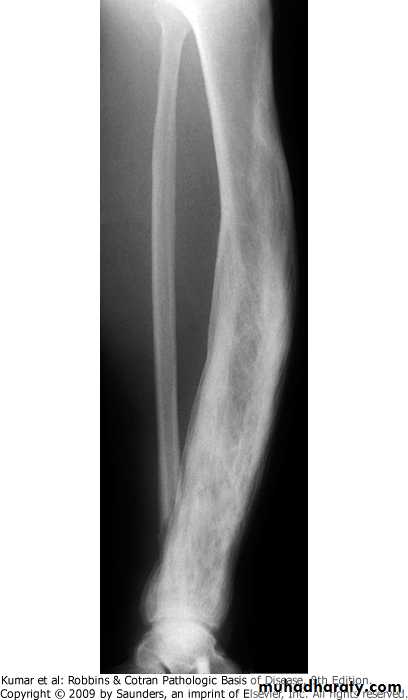

FIBROUS CORTICAL DEFECTS:.affect up to 50% of children older than 2y.developmental eccentric defects at metaphysis of distal femur and proximal tibia.about one half are bilateral or multiple .about 0.5 cm in diameter, and when they grow to about 6 cm>nonossifying fibromas>pathologic fracture .majority are asymptomatic and undergo spontaneous resolutionTibia, fibrous cortical defect